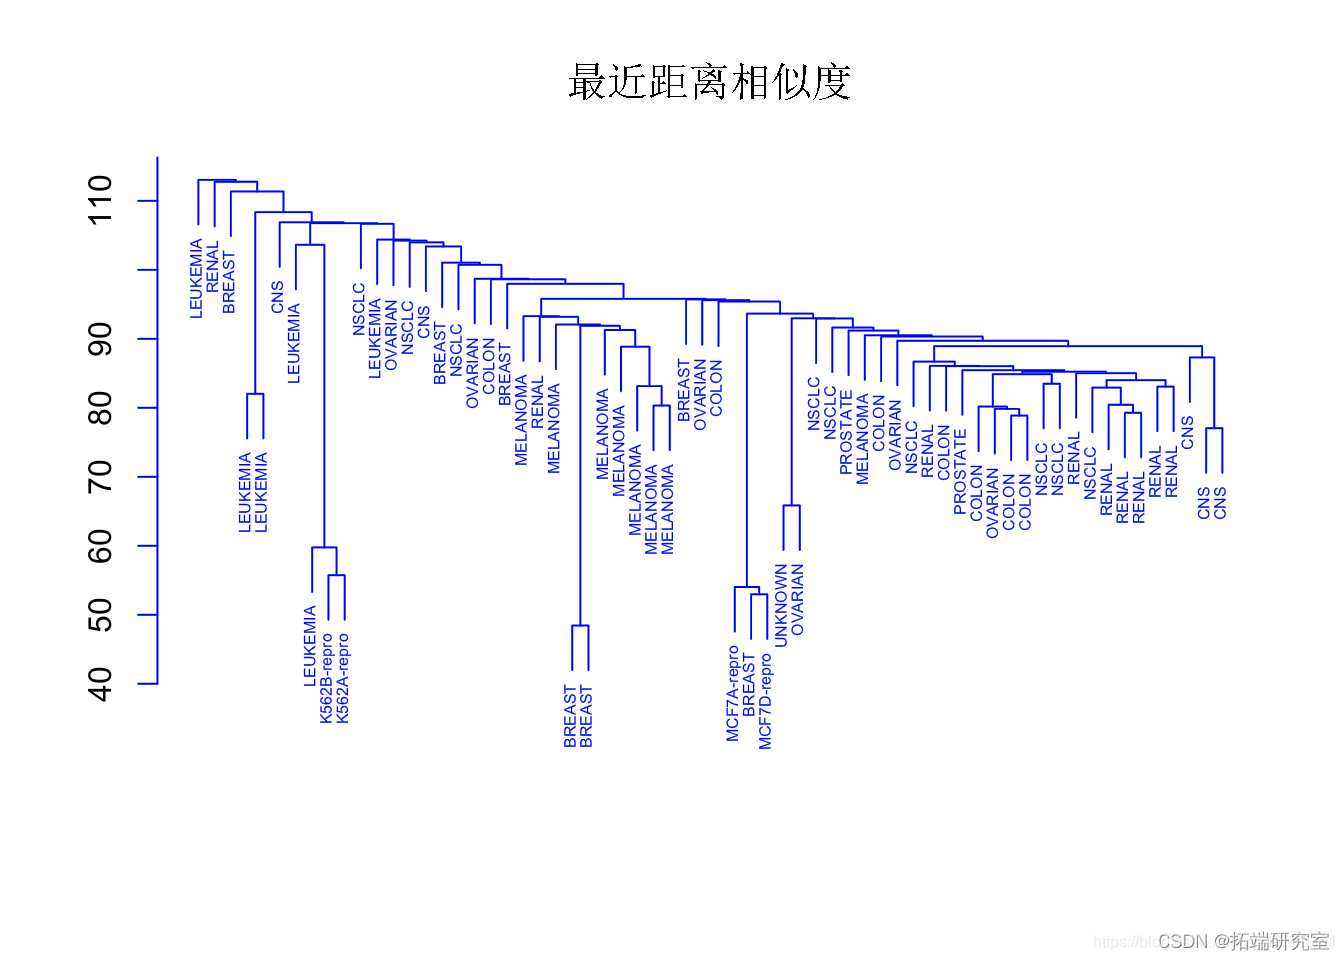

scale # 标准化变量(均值零和标准差一)。全链接、平均链接和单链接之间的比较。

plot(hclust,col="blue") #使用单链接对观察进行层次聚类。

观察结果

单链接聚类倾向于产生拖尾的聚类:非常大的聚类,单个观测值一个接一个地附在其中。

另一方面,全链接和平均链接往往会产生更加平衡和有吸引力的聚类。

由于这个原因,全链接和平均链接比单链接层次聚类更受欢迎。单一癌症类型中的细胞系确实倾向于聚在一起,尽管聚类并不完美。